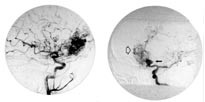

Neste dag ble det imidlertid i samråd med nevrokirurg utført cerebral angiografi, som, i tillegg til malformasjonen medialt frontalt høyre side (fig 2a), viste et stort aneurisme på a. communicans anterior (fig 2b). Hun ble overflyttet til nevrokirurgisk avdeling for endovaskulær behandling av dette store aneurismet. Fem dager senere ble hun tilbakeført til vår avdeling, og var da uten symptomer. Det er senere besluttet at behandling av malformasjonen fortsatt må ansees å være for risikabelt.